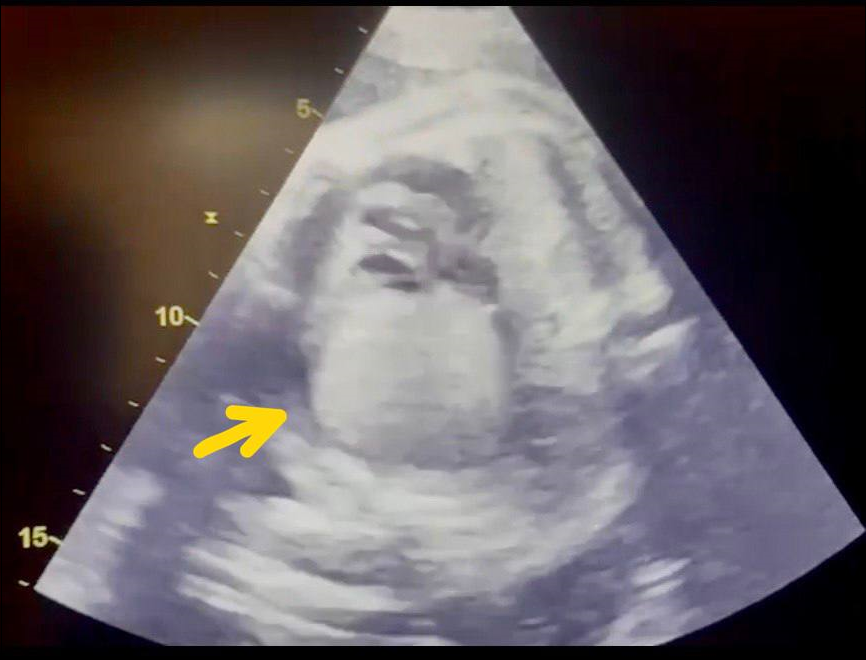

Background: Congenital heart defects (CHDs) are the most prevalent type of congenital defect. Early identification of CHDS increases postnatal treatment options and outcomes. Objective: To compare the rate of CHDS in the general pregnant population to those at high risk. It also assesses the efficacy of using periodic fetal echocardiography throughout pregnancy to test for CHDs. Methods: A prospective cross-sectional study was undertaken at the Medical City complex between September 1st, 2023, and May 1st, 2024. The fetal heart was screened antenatally during the mid-trimester. Data were gathered from 250 pregnant women, with half of them classified as high-risk due to fetal or maternal risk factors associated with congenital heart abnormalities. These parameters were compared to those seen in low-risk pregnancies to establish the need for fetal echocardiography. Results: The study comprised 250 pregnant women, with 125 in each of the low-risk and high-risk categories. The prenatal incidence of fetal cardiac disease was discovered to be 18%. Pregnancies with ultrasonography abnormalities had the highest prevalence, accounting for 37% of the overall high-risk category. In addition, 34 instances (14%) featured babies with minor cardiac abnormalities, while 6 cases (2%) involved fetuses with complicated cardiac disorders. Conclusions: The study found that CHDS is more common in high-risk pregnancies than in low-risk ones. All pregnant women, regardless of additional maternal concerns, should undergo prenatal screening, including CHDS detection.